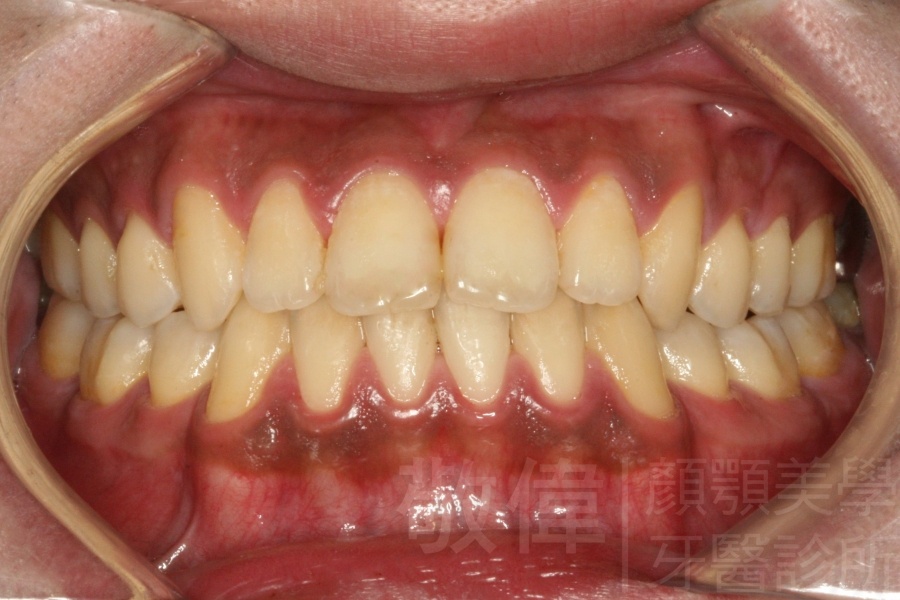

齒顏矯正/上顎暴牙且牙齒極度混亂

矯正前-右   矯正前-正   矯正前-左

矯正後-右   矯正後-正   矯正後-左

<個案說明>

上顎暴牙且牙齒極度混亂,經由矯正之後,臉型大幅度改善,牙齒的排列更加的整齊健康。相較於之前眼神充滿精神,自信心展現無遺。